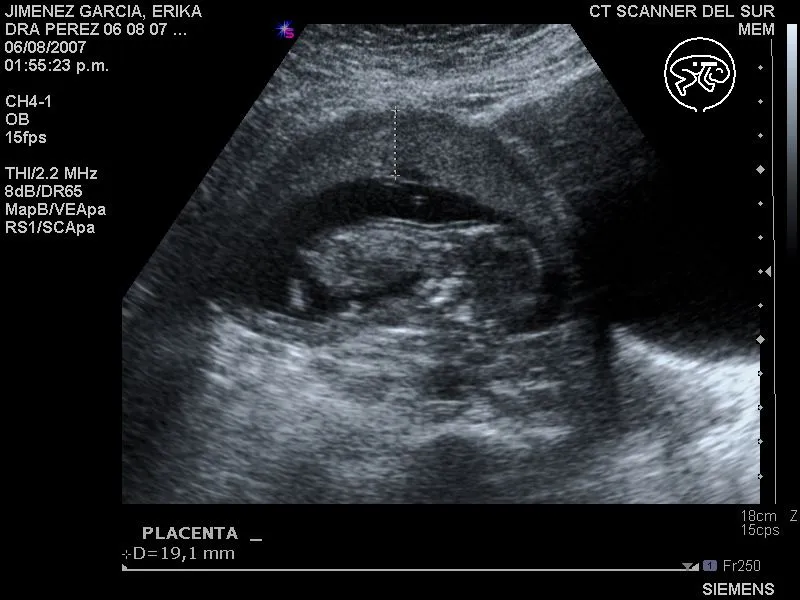

Ultrasonido bebé 3 meses

Este album de Ultrasonido bebé 3 meses con 18 fotos e imágenes no tiene descripción. Puedes sugerir una descripción de éste álbum y publicar nuevas fotos en él.

Nuestro Bebe, primer ultrasonido 2 meses gestacion.

ultrasonido 4d - Es nuestro bebe a los 7 meses bien dormidito(a ...

Gabriel Josep Combellas Fabio: Ultrasonido 3D/4D

Cronopito en camino: Mi foto de los 3 meses!!...